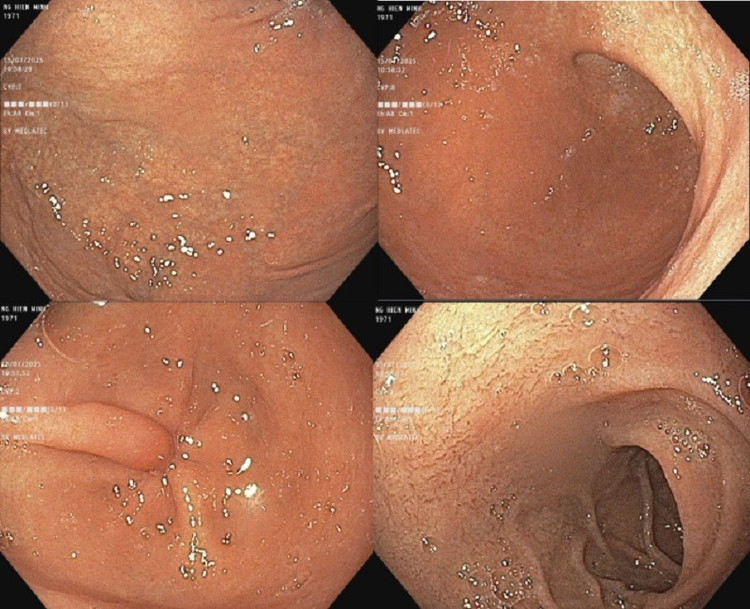

Nội soi thực quản cho thấy, niêm mạc thực quản phù nề, mất mạng lưới mạch bình thường, xuất hiện nhiều vòng đồng tâm, rãnh dọc sâu dọc theo chiều dọc thực quản, kèm theo các chấm trắng nhỏ rải rác trên bề mặt niêm mạc. Các tổn thương này là hình ảnh đặc trưng của viêm thực quản tăng bạch cầu ái toan. Bác sĩ đã sinh thiết lấy mẫu mô thực quản để làm giải phẫu bệnh và kết quả phù hợp với viêm thực quản tăng bạch cầu ái toan. Cùng với đó, kết quả nội soi dạ dày có viêm teo dạ dày (C1).

Hình ảnh nội soi thực quản của bệnh nhân/Ảnh BV medlatec